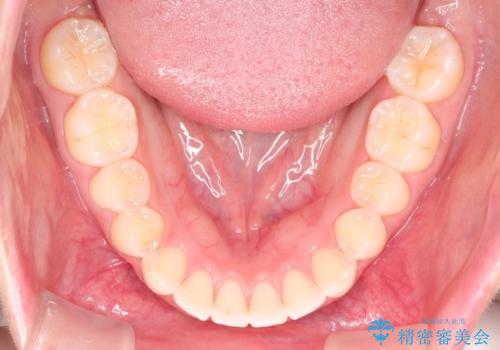

【インビザライン】前歯が出ているのを治したい

- 前歯が出ていることを主訴に来院されました。

前歯の突出感が改善され、満足していただきました。

インビザラインは20時間以上の使用が必要です。